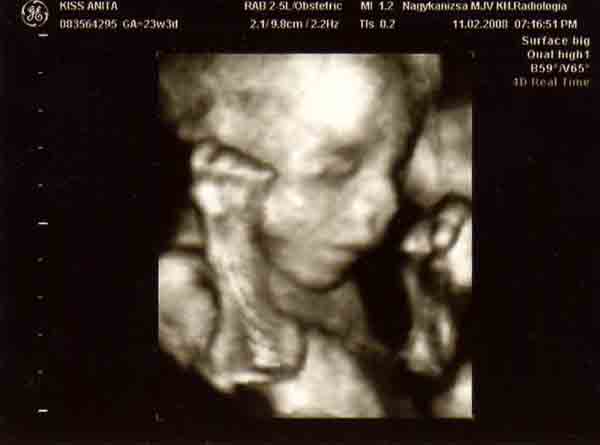

Bocsi,hogy bepofátlankodok,de mi múlt héten voltunk Kanizsán 4d-n.Tündér volt a doktornő.8000ft,20 perc a dvd és ad képeket.A Seffernél állítólag nincs kép,csak lemez.

A kanizsai telefonszám:Dr Nagy Éva 30/5265944

Kedden rendel délután fél 4-től

Mi másfél hetet vártunk,mert én kértem,hogy minél előbb mehessünk,mert ikrek és később már takarják egymást.Előbb viszont nem mertem menni,mert féltem,hogy még olyan kis ufósak lesznek.

Próbálok képet tenni róluk.

Kép [/img]

Kép

[img][img]https://www.babanet.hu/tarsalgo/attachments/1203443800.3007.jpg[/img]

Bocs,de csak külön-külön sikerült feltenni őket.[/img]

De édes babák! A mienken az arca nem látszott egyáltalán, úgy volt fordulva... :) A Seffernél voltunk, és valóban nem ad képet és 15000, majdnem duplája a kanizsainak

Nagyon édesek a törpék! És tényleg milyen jól látszódik a pofijuk.

Mi annó Veszprémben voltunk 4d-s uh-on. 10 ezret fizettünk, kaptunk videót, és 1 egész órán keresztül "szórakoztatott" minket a doki, ill. nézte, hogy minden rendben van-e. A Mátéról szembe, vagy ahol jól látszik az arca olyan kép sajnos nem készült, mert a Tóbi vagy befele fordult, vagy takarta az arcát a kezével 8) . Ennek ellenére hatalmas élmény volt. Mi egyébként 24 hetes koromban voltunk.